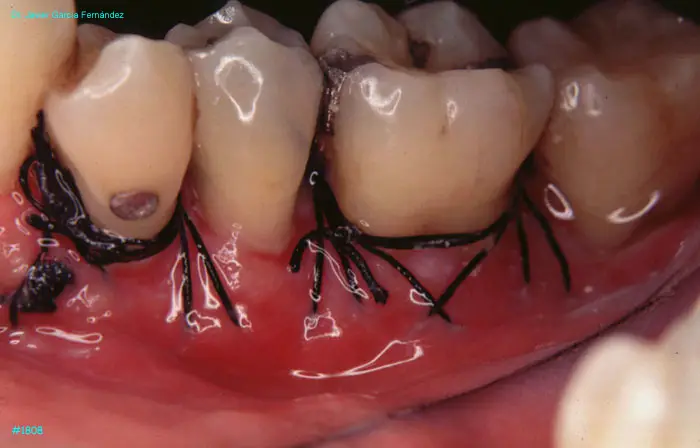

image 74